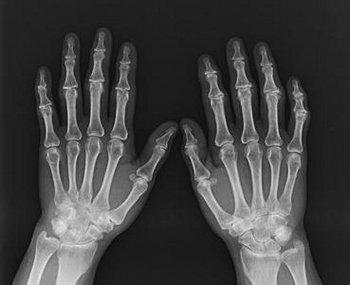

(图:类风湿性关节炎复发,万先生手部明显严重红肿)

(图:三个月的治疗,万先生已基本痊愈,恢复正常)